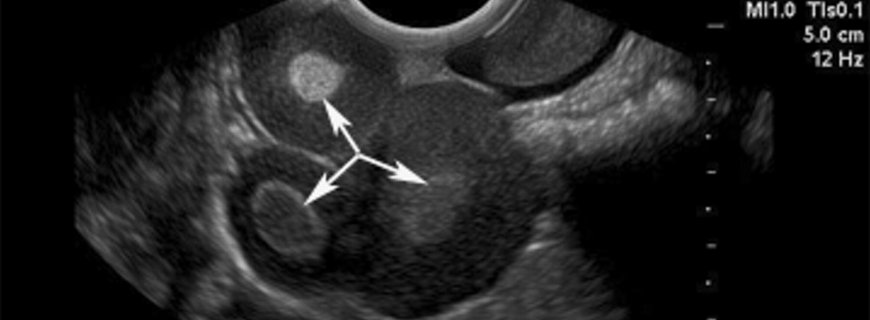

Teka Lutein Kisti Nedir ve Neden Oluşur?Teka lutein kistleri yumurtalıkları ılımlıdan çok büyüğe kadar büyüten fizyolojik yumurtalık kistleridir. Genellikle yumurtalıkların hormonlar tarafından çok uyarılmasına (tüp bebek tedavisindeki gibi) ya da yu...